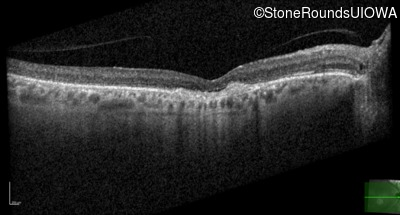

Optical Coherence Tomography - Right - 20/100

Exemplar / OCT Stack